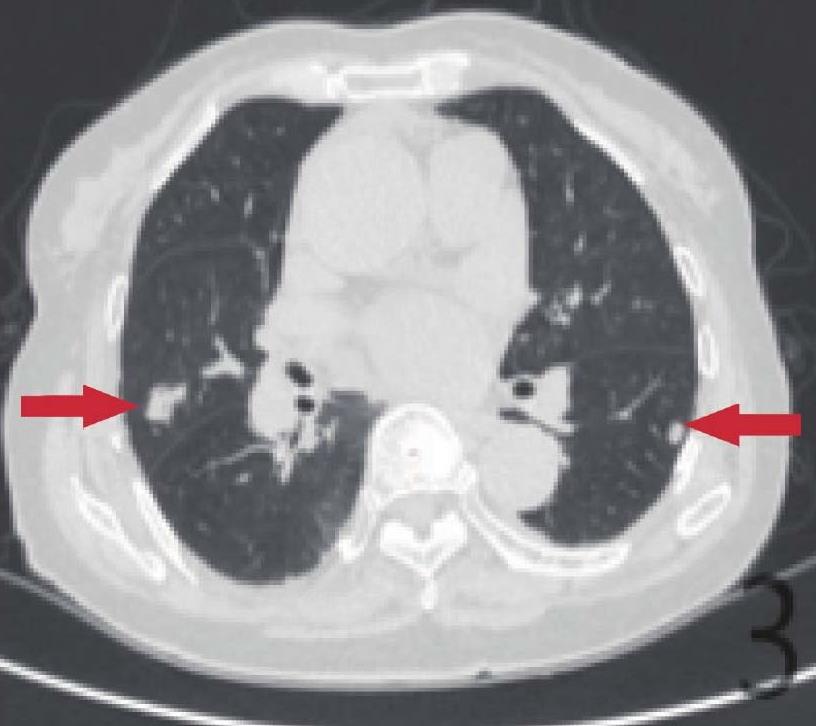

c.肾癌术后肺转移